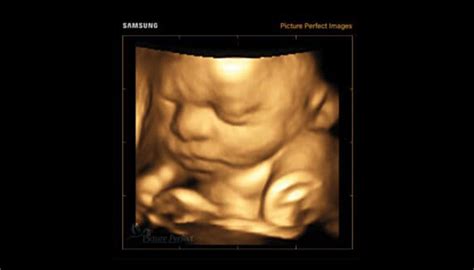

O altă situație care necesită controale regulate, la anumite intervale, este sarcina. După confirmarea sarcinii de către medicul obstetrician, acesta va recomanda viitoarei mame investigațiile suplimentare necesare, specifice fiecărui trimestru de sarcină și fiecărei gravide în parte. Medicul va monitoriza clinic și ecografic atât mama, cât și viitorul bebeluș, asigurând o evoluție optimă a sarcinii.